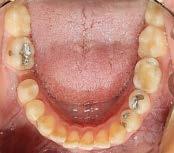

De frente (Figura 7) presenta líneas medias dentales no coincidentes, 6 mm overjet, 10% overbite, relación molar y canina clase II bilateral. Las oclusales (Figura 8) la arcada superior de forma triangular, presencia de OD 53 y apiñamiento severo, la arcada inferior de forma cuadrada con segundos molares en erupción y apiñamiento moderado.

Figura 5. Corte coronal. Figura 6. Corte sagital. Figura 7. Intraorales de frente, lateral derecha e izquierda. Figura 8. Vista oclusal superior e inferior.

Se observa la liberación del apiñamiento superior e inferior, ( Figura 14) se incluyó el OD 13 al arco y se consiguió la forma oval de ambas arcadas.